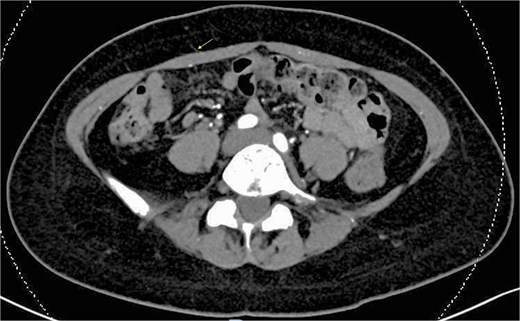

Computed tomography angiography (CTA) of the abdomen was performed, which demonstrated three perforators on each side, with a maximum diameter of 1 mm (Fig. 1). The perforator locations were marked following corroboration with bedside doppler ultrasound (Fig. 2).

Preoperative CT angiography showing small maximum perforator diameter of 1 mm (arrow).